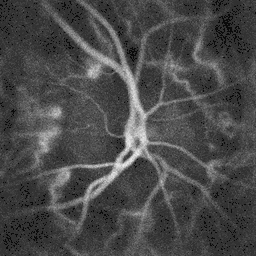

Ophthalmoscopy photograph showing the optic disc as a bright area on the right where blood vessels converge.